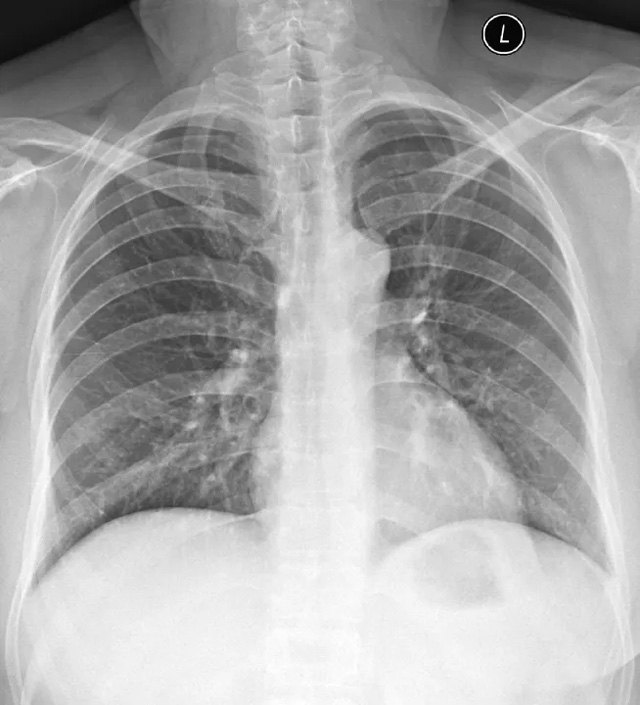

X線定位真空輔助旋切術(shù)是對臨床觸診和B超檢查均為陰性而X線片顯示的微小病變在X線立體定位引導(dǎo)下,將真空旋切刀置入乳腺可疑病灶區(qū)進(jìn)行旋切及組織病理學(xué)檢查的一種乳腺微創(chuàng)新技術(shù)。

乳腺X線檢查發(fā)現(xiàn)可疑微小鈣化病灶成簇分布,BI-RADS:4類,且患側(cè)乳房臨床觸診和超聲檢查均為陰性。

DR技術(shù)成像快、空間分辨率高,圖像清晰、細(xì)膩,是臨床不可或缺的常用基礎(chǔ)檢查技術(shù)。DR基礎(chǔ)成長營系列網(wǎng)絡(luò)課程,主要聚焦于臨床應(yīng)用中大家關(guān)心的DR圖像質(zhì)控、標(biāo)準(zhǔn)擺位及雙能成像技術(shù),助力拍攝優(yōu)質(zhì)的DR圖像,提供更多影像診斷信息,服務(wù)于臨床診斷。